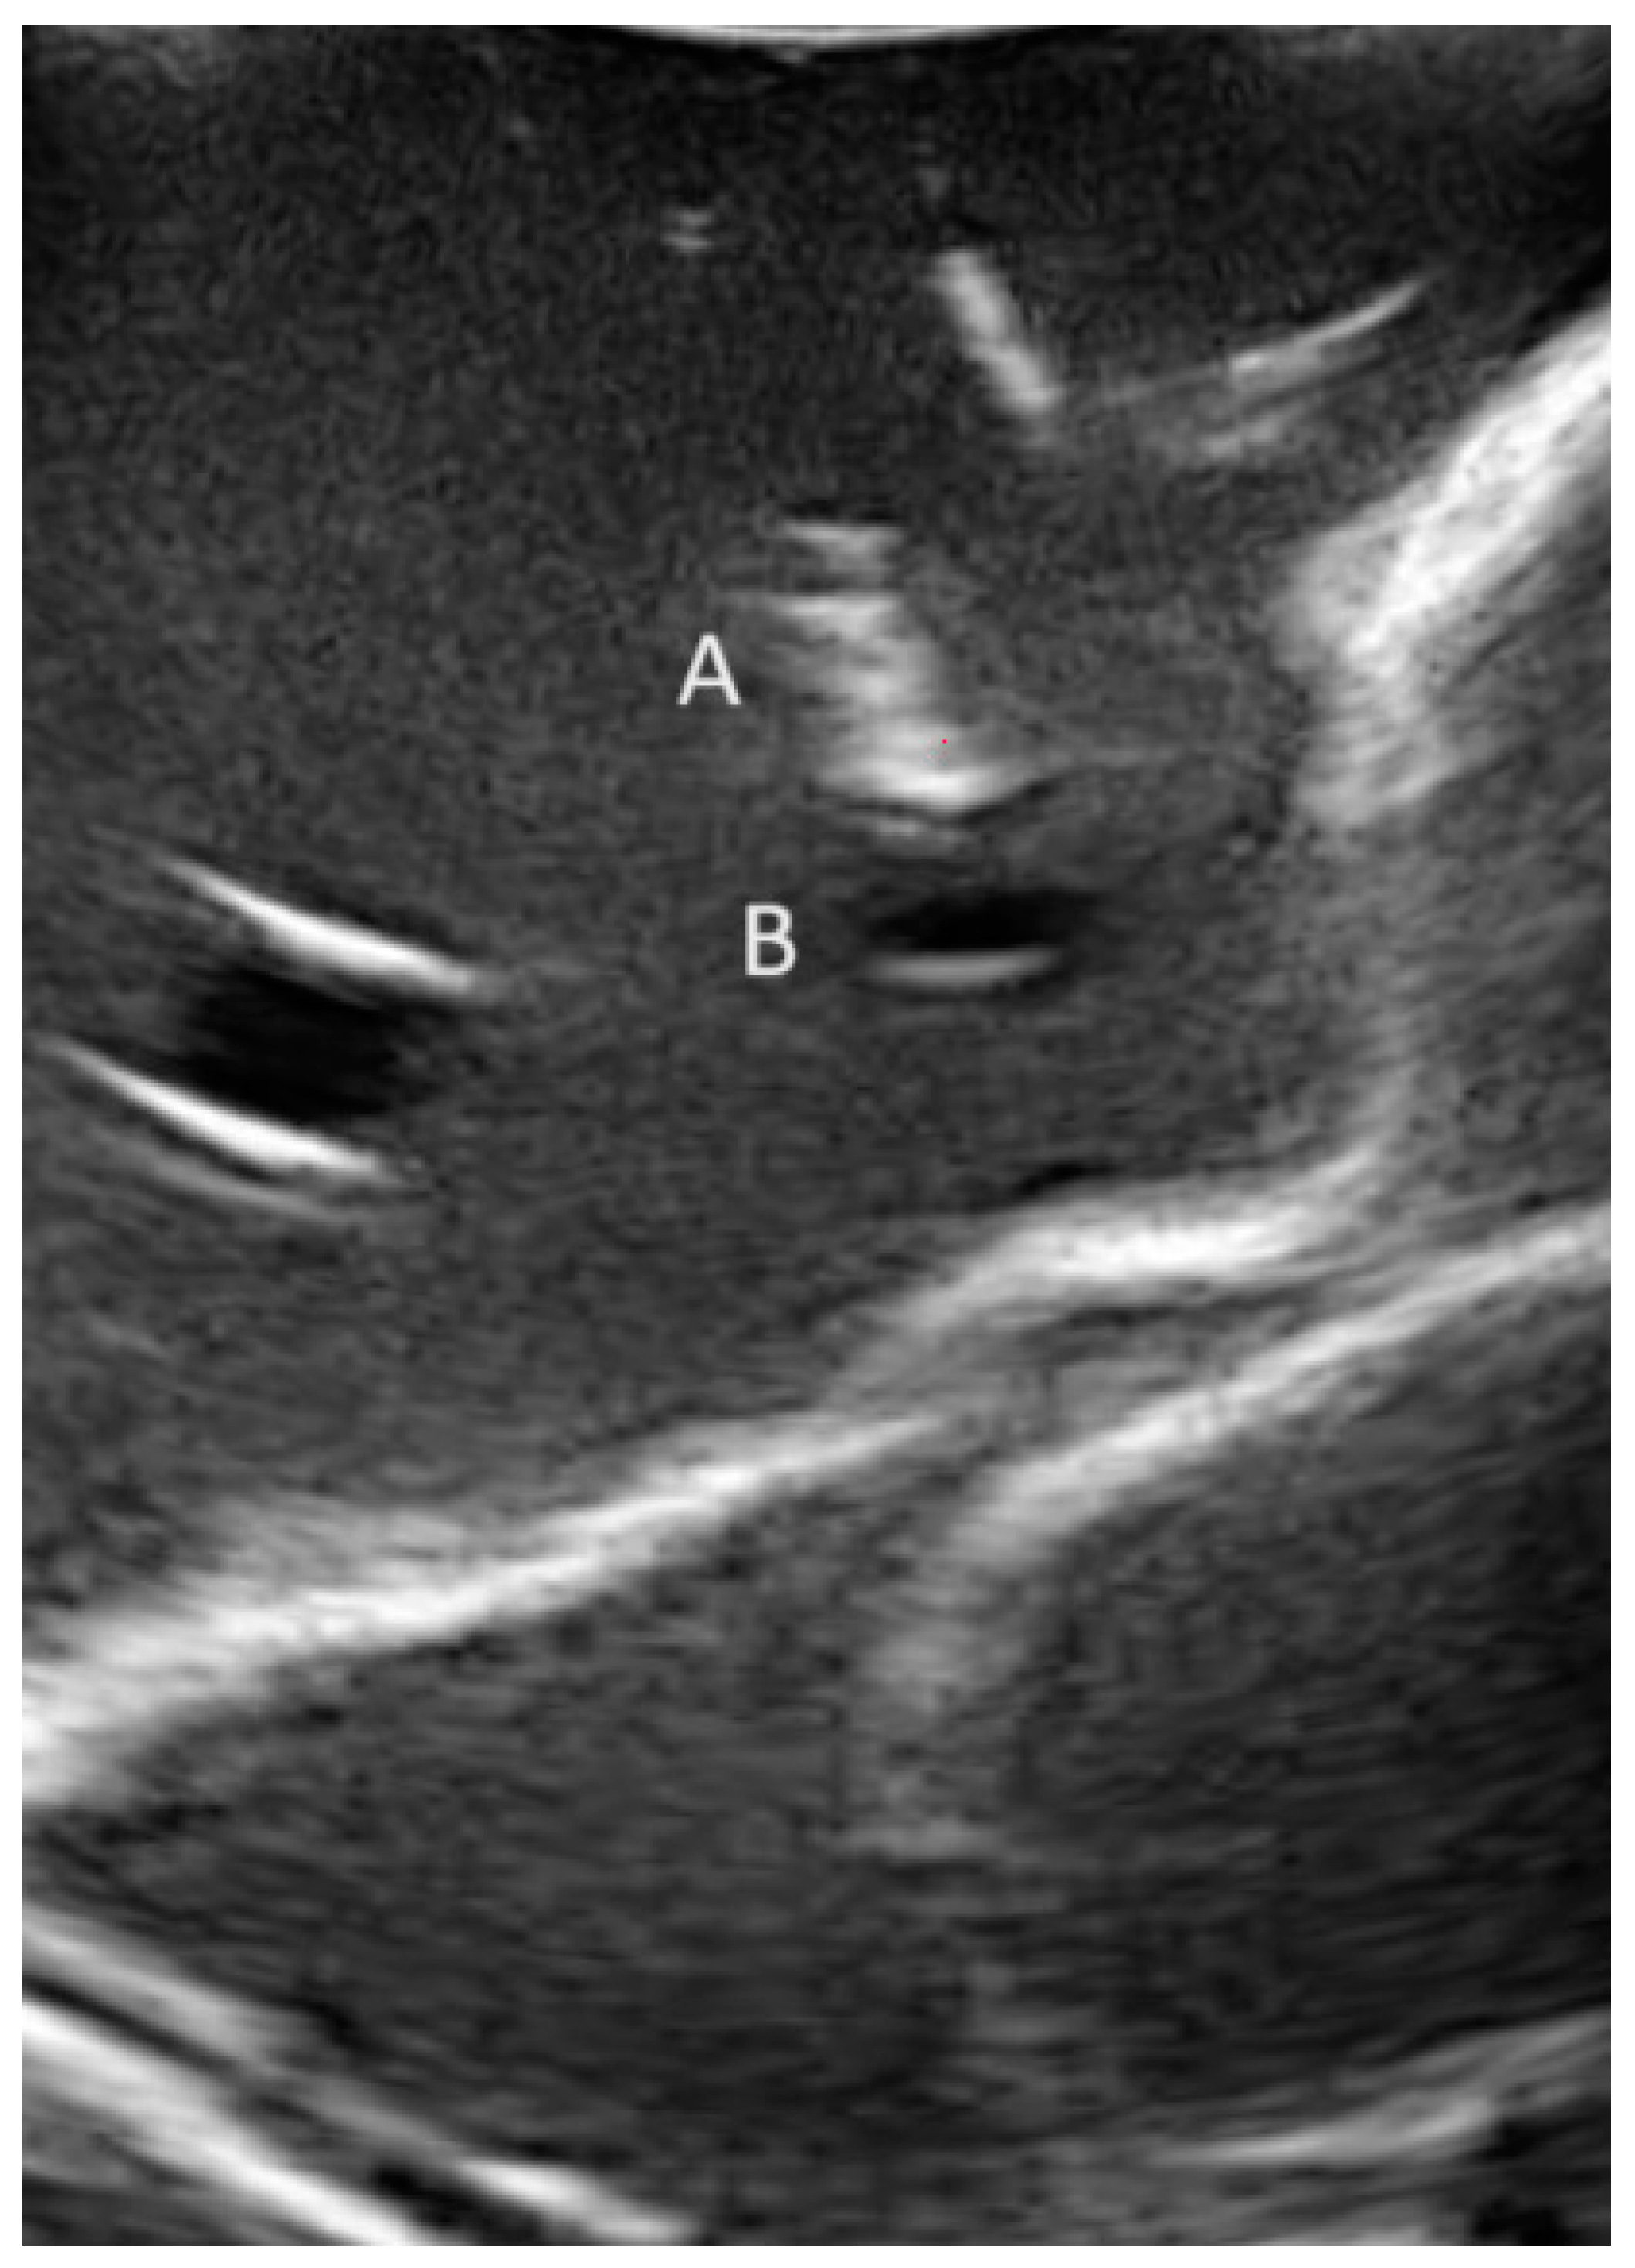

2.1. Phantom Model